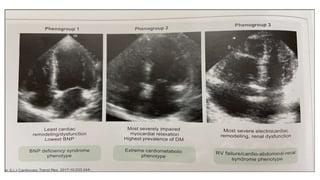

This document provides an overview of heart failure. It begins by outlining the objectives of understanding pathophysiology, classification, therapeutic targets, and initiating guideline directed medical therapy. It then discusses the anatomy, myocardial mechanics, effects on physiology, and introduction to heart failure. Classification systems such as ESC and AHA/ACC are presented. The document discusses heart failure in India, hospitalization risk, definition, and why ejection fraction is used for classification. It covers the pathophysiology, signs and symptoms, assessment, biomarkers, ECG, CXR findings, echocardiogram evaluation, treatment approaches for acute and chronic heart failure, guideline directed medical therapies including drugs, and SGLT2 inhibitors.